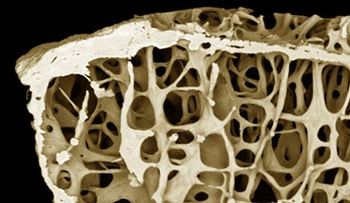

Bisphosphonates offer women no protection against breast cancer but do help prevent fractures related to osteoporosis.

Despite earlier observational studies, bisphosphonate treatment for 3 to 4 years appears not to decrease the risk of invasive postmenopausal breast cancer, according to a new study in JAMA Internal Medicine.